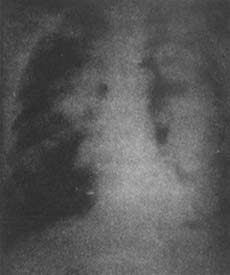

肺包蟲病X線表現

肺包蟲病X線示意圖如囊腫破裂,內容物咳淨,又未發生感染,胸片上表現為薄壁邊緣光滑的含氣囊腫。以後囊腔逐漸縮小,僅留有一些纖維化陰影。如囊腫破後發生感染,則囊壁增厚,周圍有慢性炎症出現的可見肺浸潤片狀影。如破入胸腔,有胸腔積液或液氣胸。